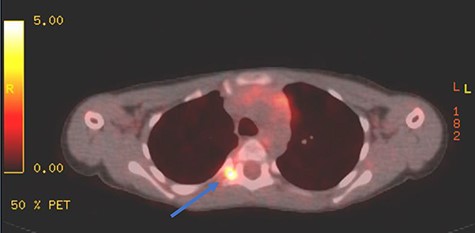

PET scan showing area of focal enhancement at the level of the tumor.

Appropriate tests were done (vanillylmandelic acid and norepinephrine metabolites were found to be slightly high, urine metanephrines were within normal limits, insulin-like growth factor-1 (IGF-1), IGF-binding protein, adrenocorticotropic hormone, cortisol and growth hormone levels were all normal. During her clinic follow-up 6 months post resection, a positron emission tomography (PET) scan showed hypermetabolic activity in the soft tissue at the level of T5 and adjacent right costovertebral junction with possible residual tumor and T5 involvement (Fig. 3). Magnetic resonance imaging was carried out after and showed significant narrowing of the spinal canal at the level of T5 and T6 and focal signal intensity at T5 suggestive of bone involvement (Fig. 4).